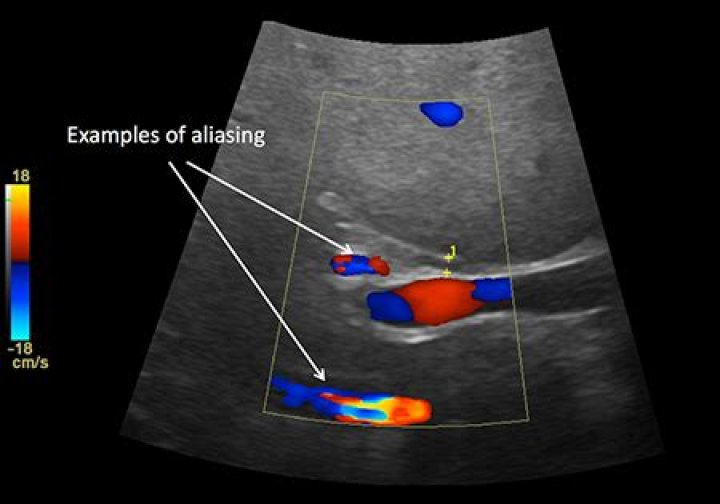

In sonographic. Doppler, the result of aliasing is an apparent change in direction of blood flow in. high-velocity areas, producing flow that appears to be